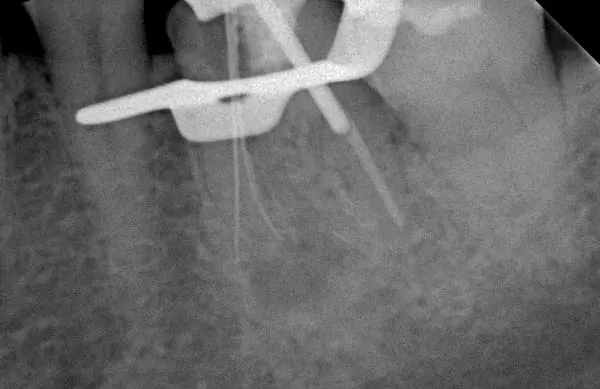

顯 微 根 管 治 療 前